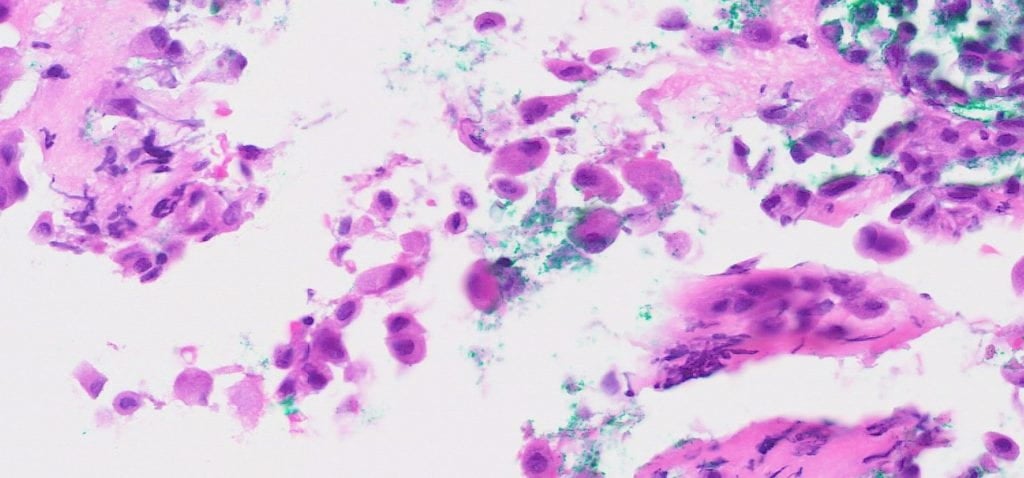

The lesional cells are of mesothelial origin, as indicated by their retention of skirting and windowing, their ovoid nuclei and dense cytoplasm and the lack of a clear cut second lesional population. In the absence of a cell block for further workup, the most prudent interpretation would be to suggest the presence of atypia and recommend clinical correlation and the option of biopsy for further workup.

Subsequent peritoneal biopsy performed showed the presence of atypical sheets of mesothelial cells infiltrating into fibroadipose tissue. Immunohistochemical staining confirmed mesothelial nature, as well as BAP1 loss (no loss of p16 with FISH). Findings were thus best in keeping with malignant epithelioid mesothelioma.

This case highlights a situation where mesothelioma may not present as a cellular yield of crowded three-dimensional groups, but as singly dispersed cells with more subtle atypia. Thus, diagnosis would be more reliant on cytomorphology of individual cells. Some tips for recognising the differences: